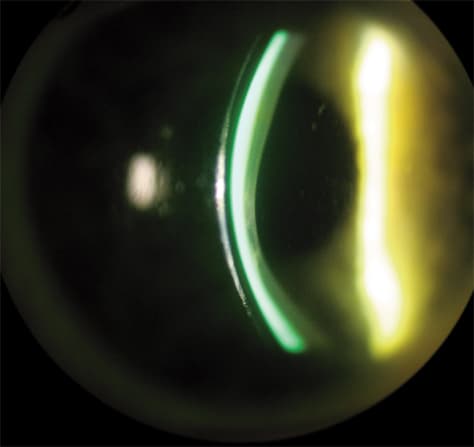

Scleral RGP contact lenses (Figure 3), which are defined as having a diameter of 18 mm to 24 mm, are making a comeback into mainstream specialty-lens fitting. Their inherent advantage to fitting irregular corneas is that they rest on the sclera and vault the corneal surface. This provides the patient with comfortable wear and stable vision. They trap a tear reservoir (Figure 4) that not only masks corneal irregularity, but also can act as a bandage for the anterior surface. The best way to begin fitting these lenses is to call an RGP laboratory that makes them, such as Medlens Innovations or Essilor of America Inc. (Dallas) and purchase a trial lens set, using their fitting guide for reference. When you first start using these lenses, consultation with the lab will be critical to your success during the learning curve.

Figure 4. Scleral RGP contact lenses also trap a tear reservoir that masks corneal irregularity and acts as a bandage for the anterior surface.

Therapeutic Scleral RGP Lenses